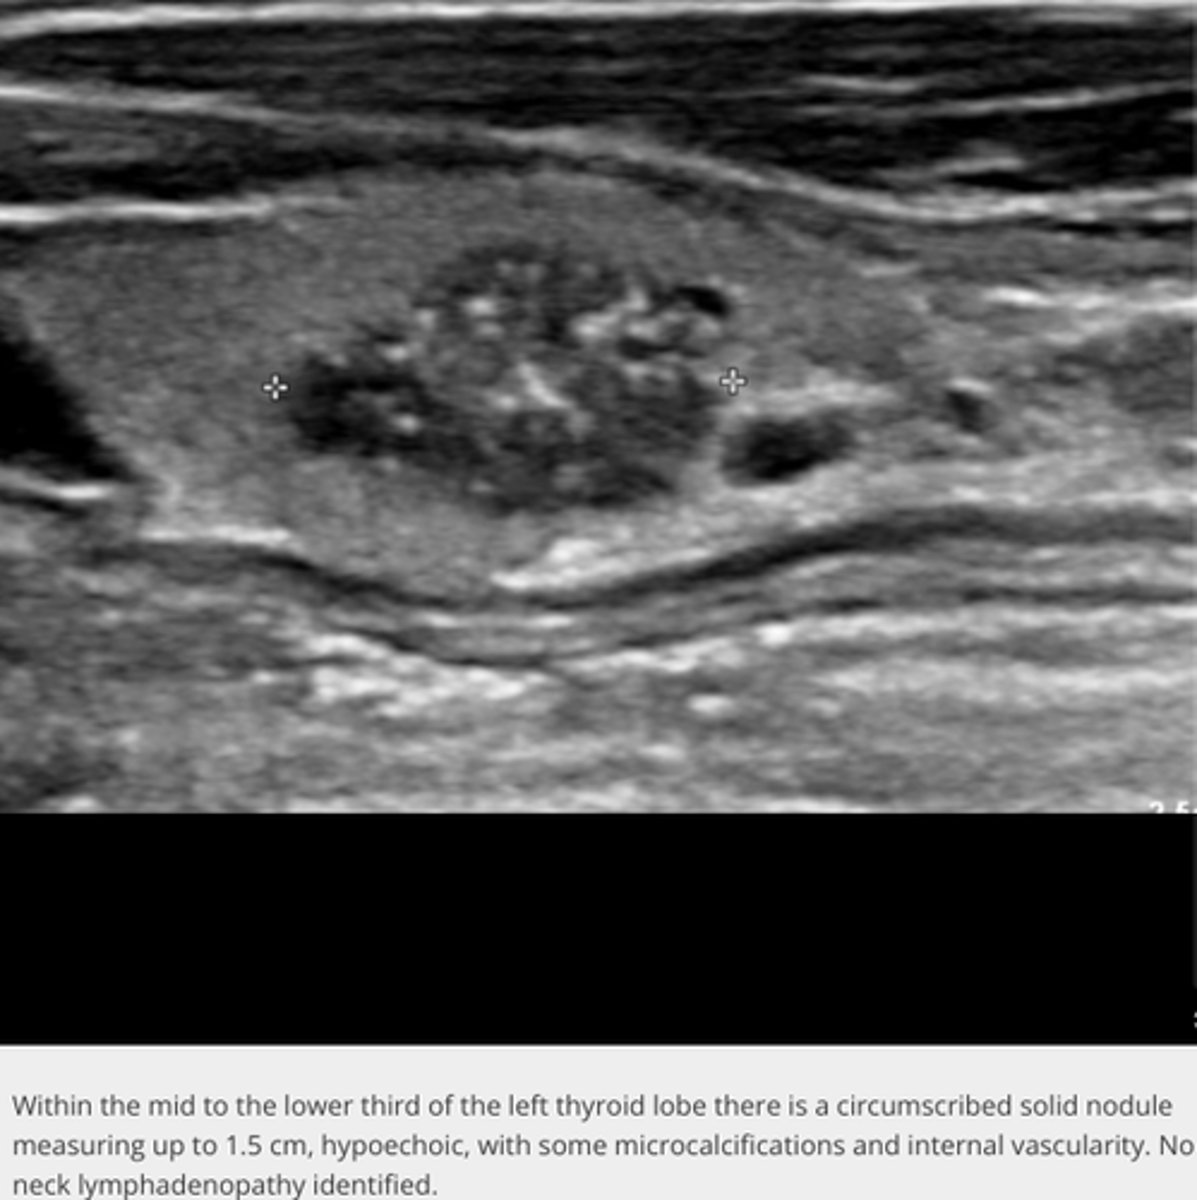

Malignant Thyroid Neoplasms - Carcinoma:

Etiology

-_____ (80%)

-_____ (5-15%)

-_____ (5%)

-_____ (2%)

Clinical findings

-Palpable _____ mass

-_____

-Neck pain

-Lymphadenopathy

Sonographic findings

-_____echoic mass

-_____ borders

-Thick _____ peripheral halo

-May degenerate

-Increase in _____ from previous exam

-_____ to cervical lymph nodes, lung, bone, and larynx

-Papillary (80%)

-Follicular (5-15%)

-Medullary (5%)

-Anaplastic (2%)

-Palpable neck mass

-Dysphagia

-Dyspnea

-Hoarseness

-Hypoechoic mass

-Irregular borders

-Thick incomplete peripheral halo

-Microcalcification(s)

-Increase in size from previous exam

-Metastases to cervical lymph nodes, lung, bone, and larynx